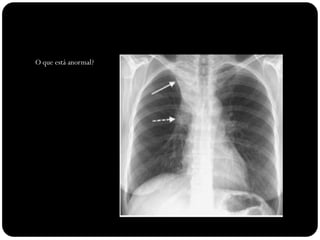

O que está anormal?

Atelectasia LSD

Sinal do S de Golden

Causado por

carcinoma

broncogênico

Note deslocamento

da fissura menor,

elevação da cúpula

diafragmática

direita...